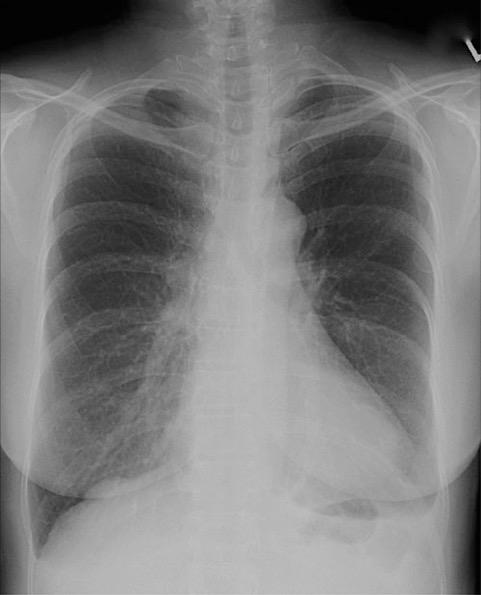

The figure below demonstrates which of the following conditions?

dextrocardia